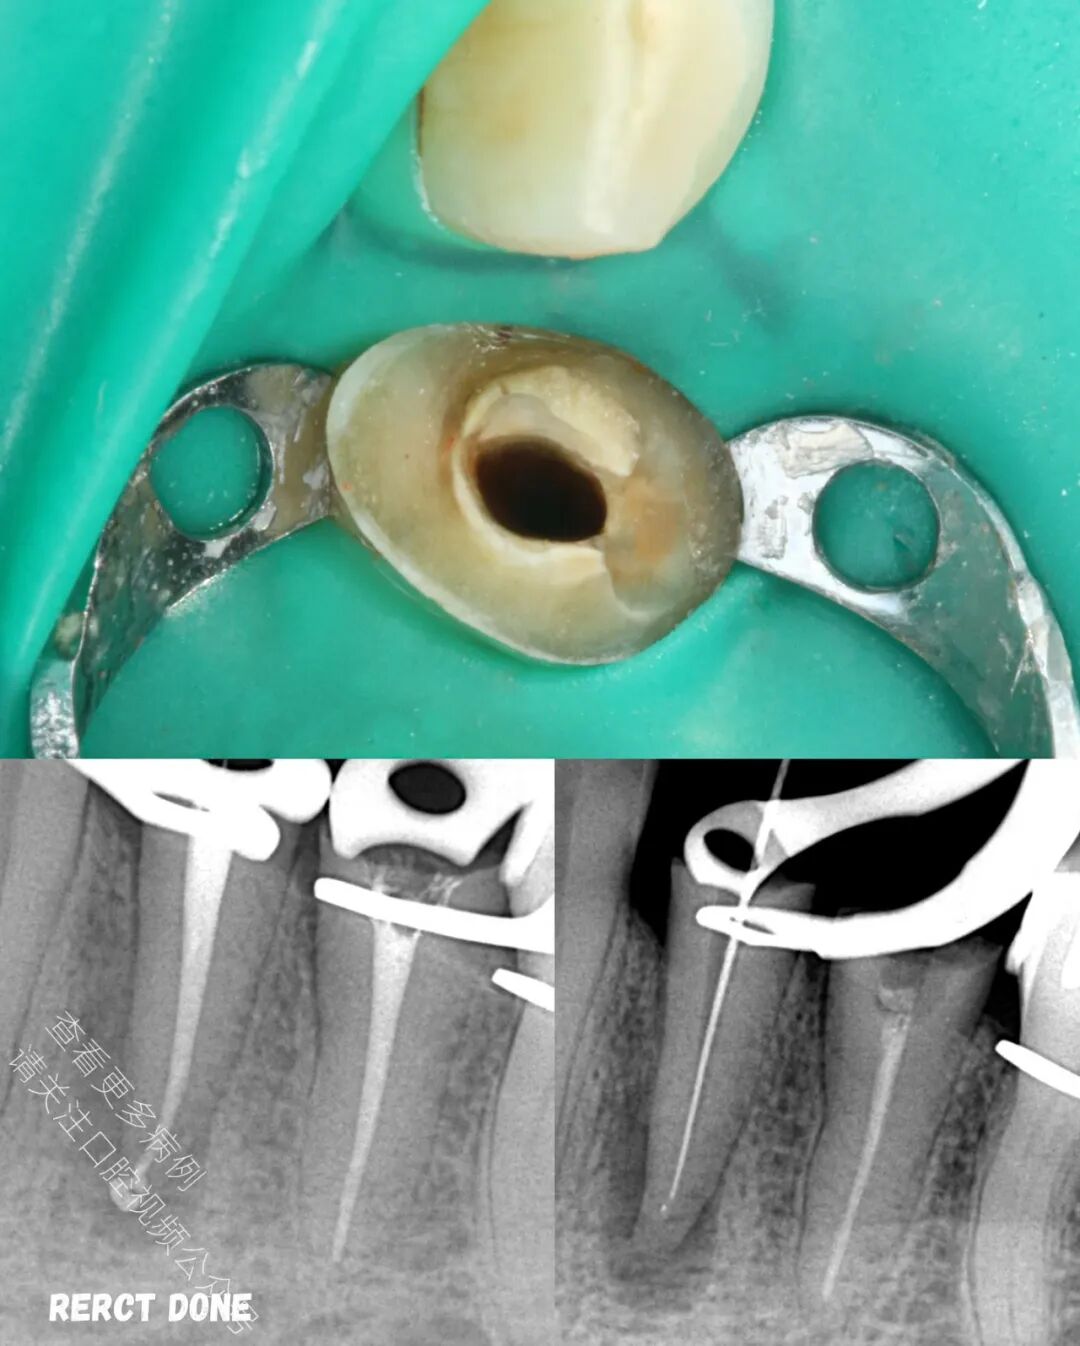

🪄 成功使用橡皮障隔离,对两颗前磨牙进行了再根管治疗(ReRCT)

🪄 术后X光片显示冠修复体边缘密合良好,修复效果理想